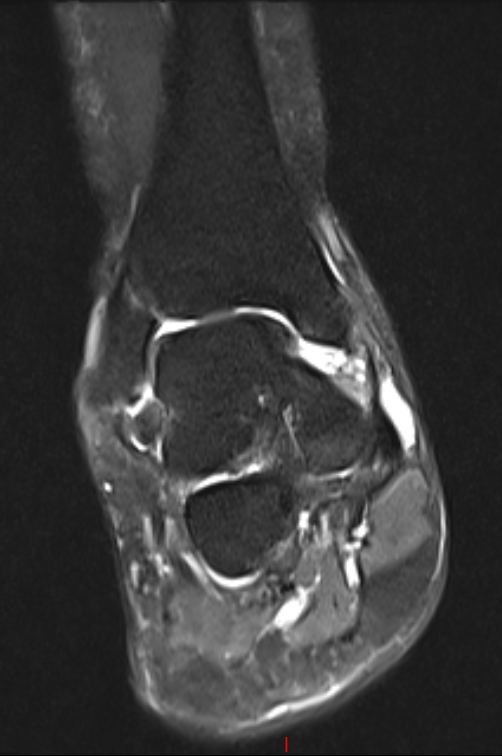

术前磁共振

术前CT